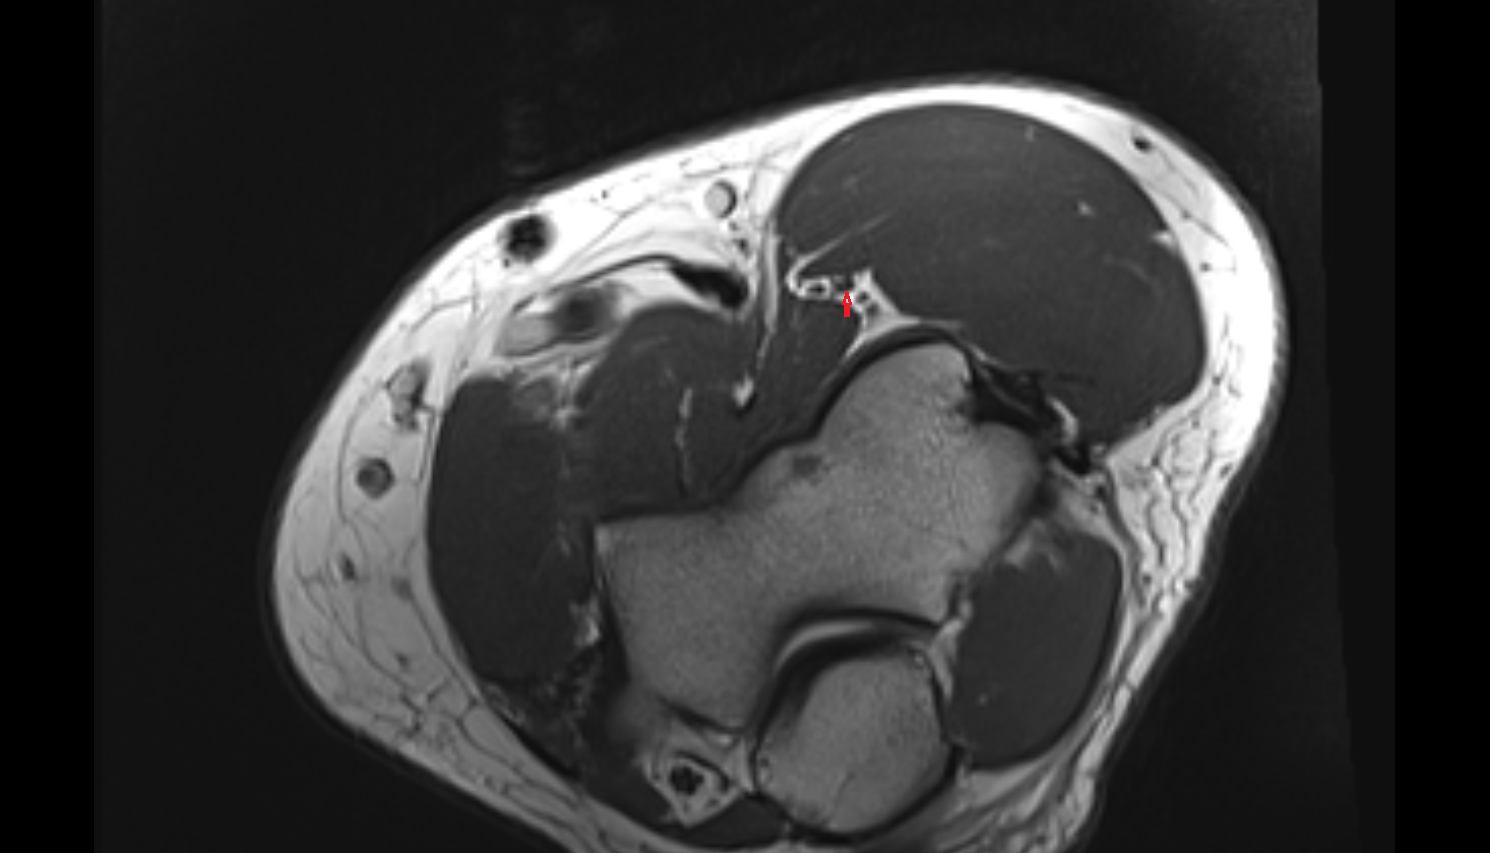

- Knee Joint